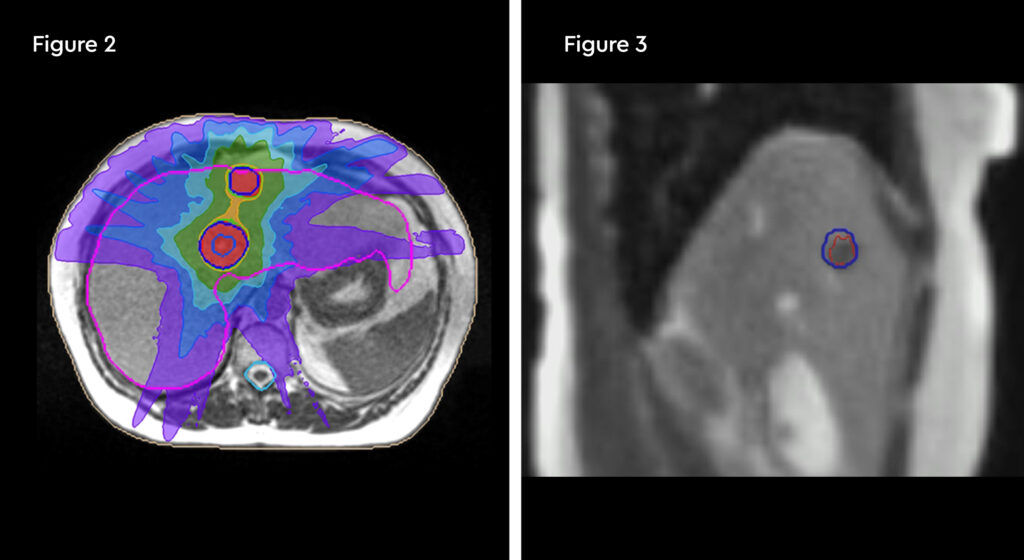

MRIdian treatment

SABR treatment on the MRIdian was prescribed at 40 Gy in five fractions, with the aim of achieving local control. This was completed at the end of January 2020.

Fig 1: Anatomical location of the recurrent tumour and the critical organs at risk

Fig 2: Radiation treatment plan down to 50% isodose

Treatment commenced within two weeks and was delivered over five days over a two-week treatment period. The patient travelled from her home in Hertfordshire for daily treatment. At each session the target and organs at risk (OARs) were recontoured and the plan was optimised to minimise dose to normal tissues. Due to complexity, treatment took 90 – 120 minutes to complete from set-up, plan adaptation and treatment delivery, during which time the patient remained on the bed.